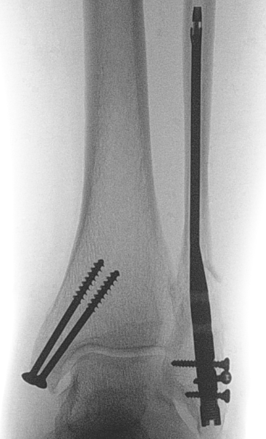

Isolated Weber C fracture

Weber C fracture Weber C fracture with deltoid ligament injury

Maisonneuve injury: proximal fibula with open medial clear space

Definition

Fracture above syndesmosis

Syndesmosis disrupted +/- deltoid ligament

Syndesmotic injury

Management

ORIF fibular

Syndesmosis reduction and stabilization with plate versus screws